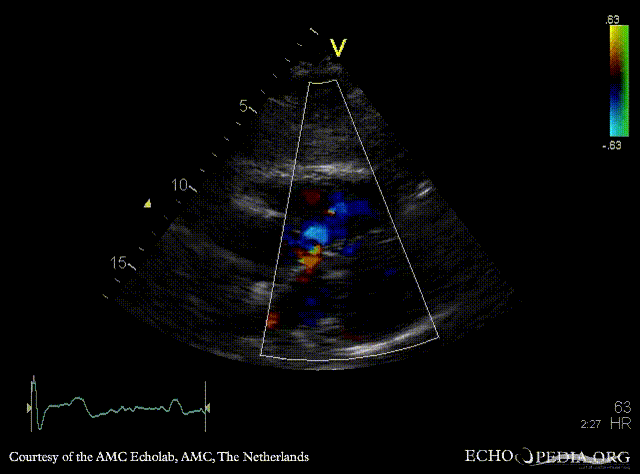

| PSAX: ASD type I | Subcostal view: ASD type I |